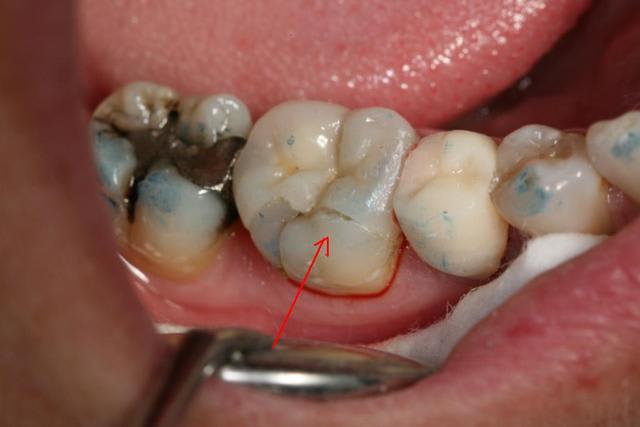

Après avoir revu la patiente aujourd'hui...

Je peux dire que oui, il faut que je reprenne le mauvais ajustage en vestibulaire (indiqué par une fleche rouge sur la photo) mais c'est le seul endroit (c'est déjà pas mal me direz-vous) qui n'est pas parfaitement ajusté.

La patiente a même du trouver ca bizarre, vu le temps que j'ai regardé l'onlay avec ma sonde à la recherche d'un hiatus ou d'un joint de colle épais.

Maintenant c'est sur qu'une colle transparente, pardonne moins d'erreur visuelle qu'une colle de la teinte de l'onlay !

J'ai pris d'autres angles de vue de cet onlay tant critiqué (au moins ca fait débat et moi cela me permet de réfléchir)... Et puis si vous êtes trop méchant je retourne en chir :+))